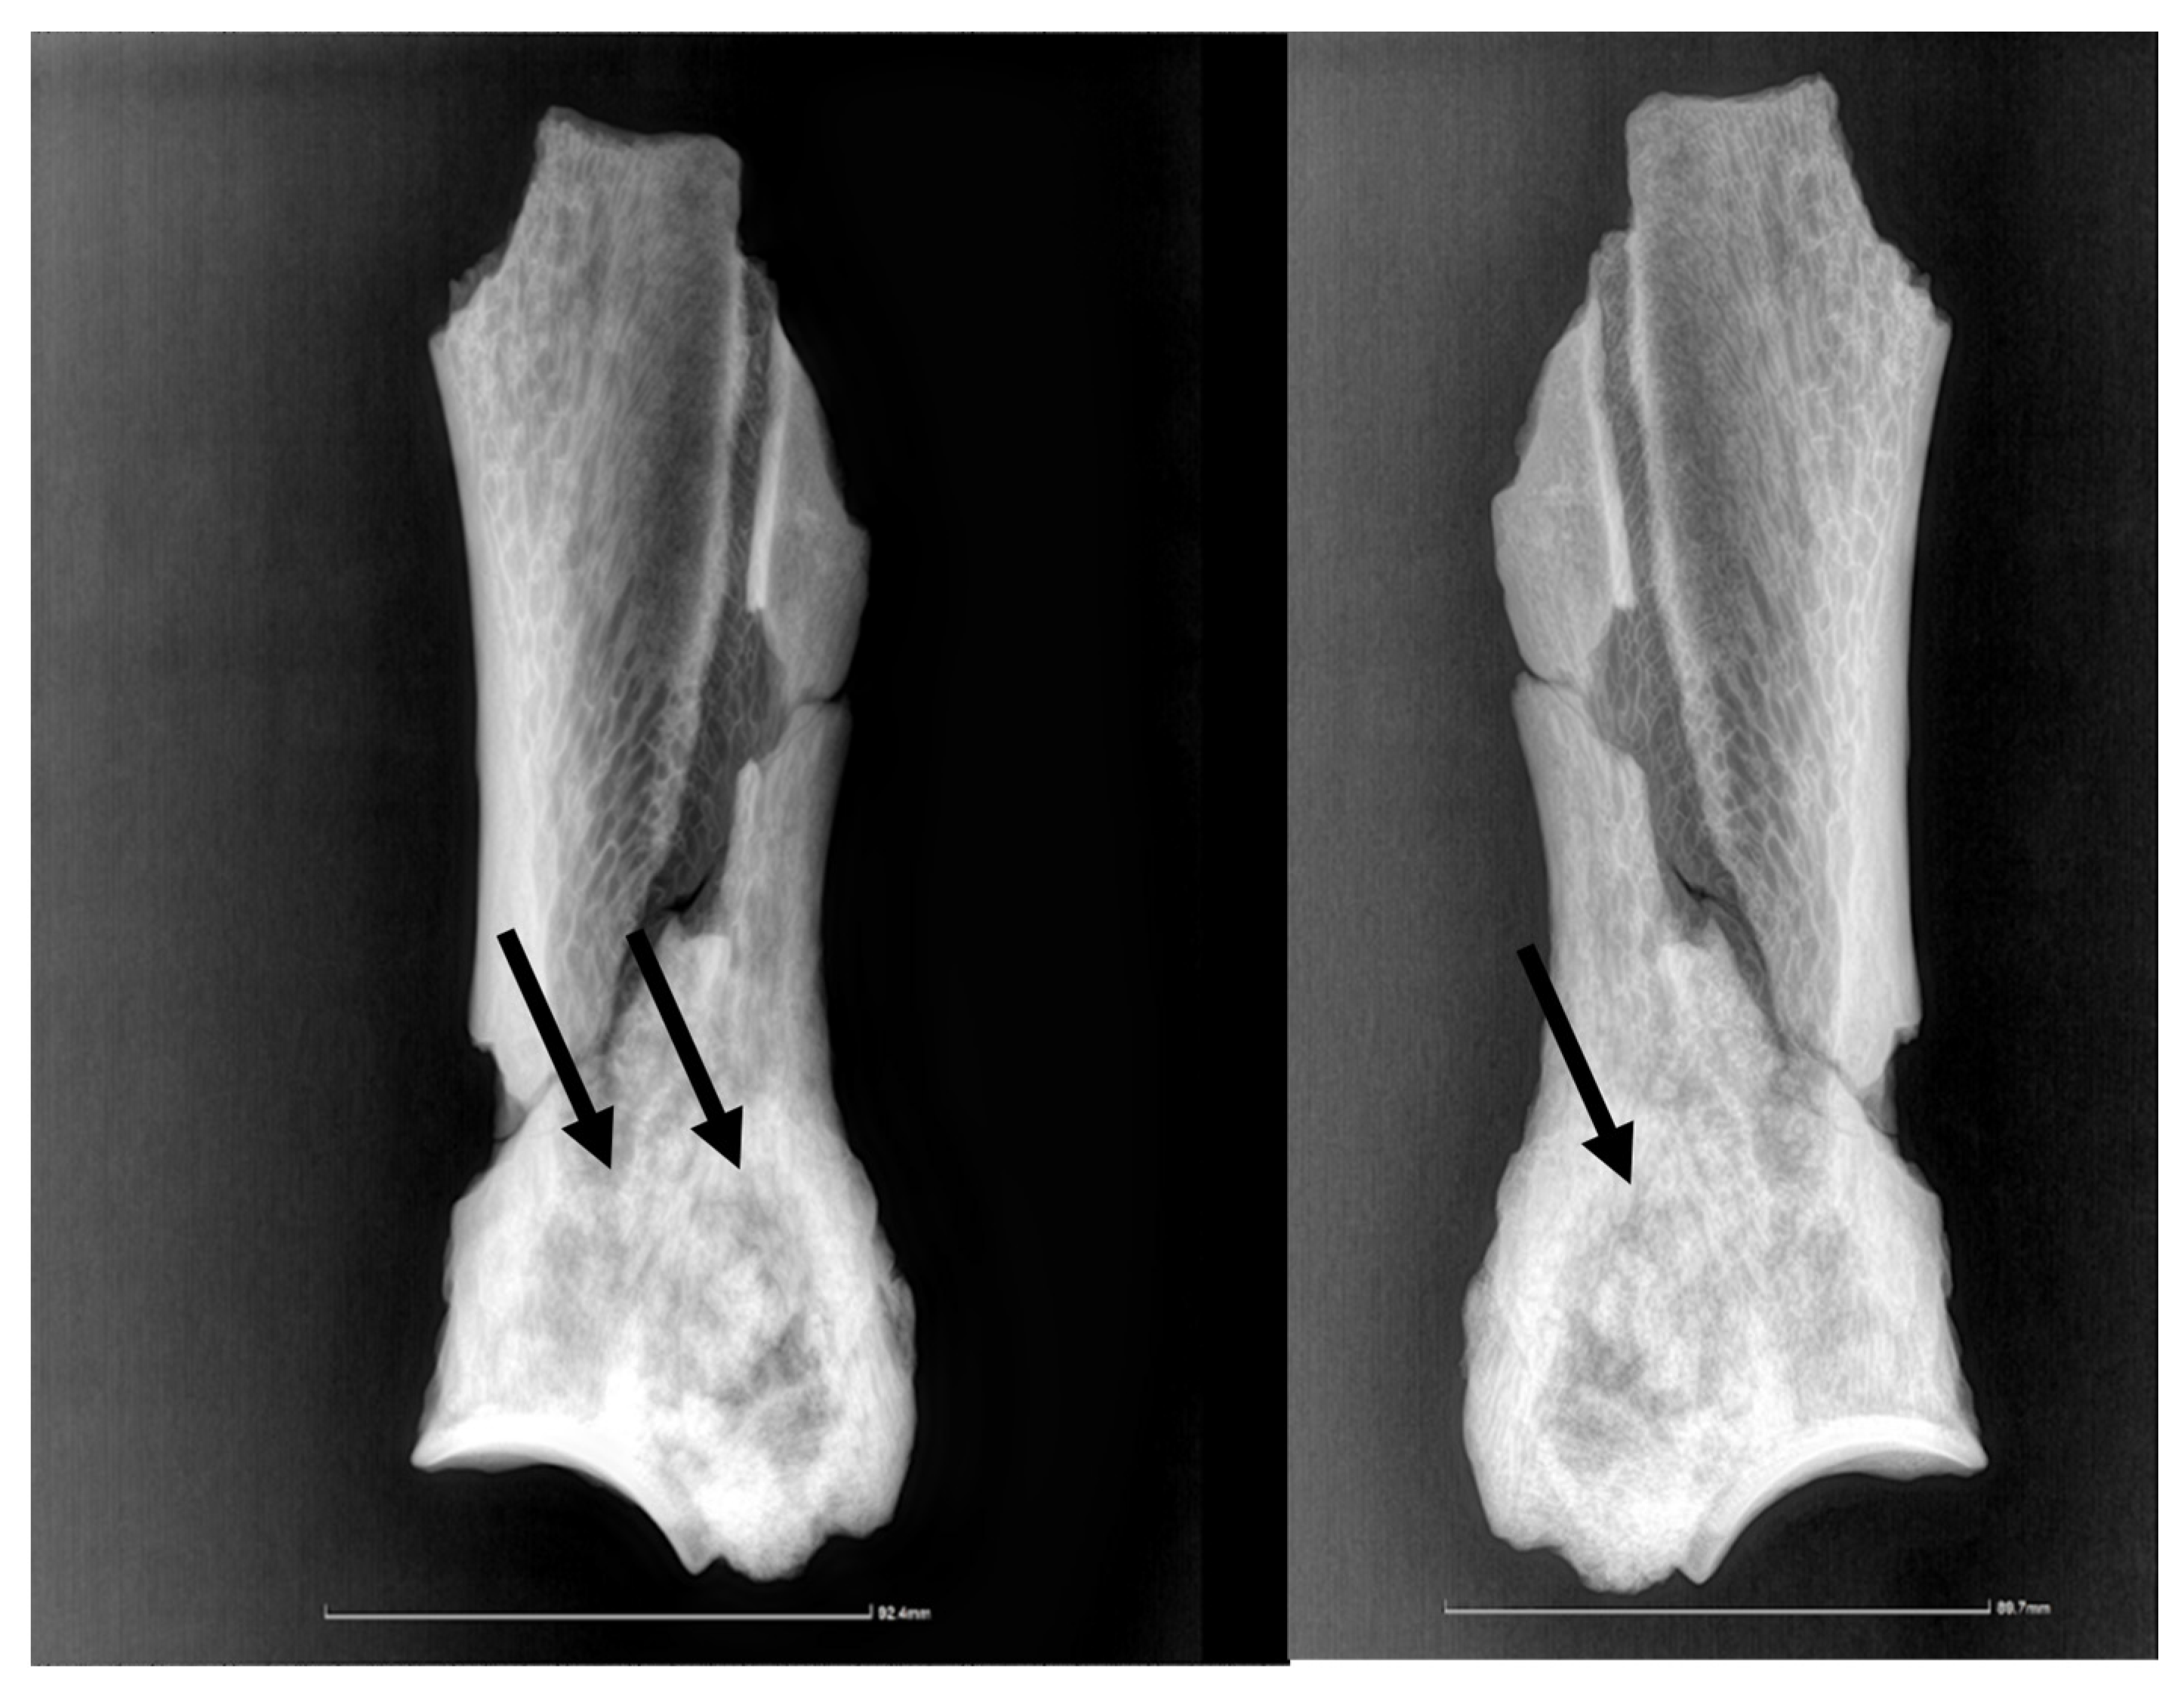

3.2. Description of the Imagistic Investigation

The radiological investigation showed (Figure 2), as expected, just densification of the bony structures around the scapular neck, with no possibility of a clear link to a pathological situation. There is a lack of differentiation among the neighboring structures, such that the supraglenoid tuberosity and its usually much denser structure are hard to tell apart from the surrounding tissue. The borderline between the denser, newly deposited bone is visible also on the radiographic images, especially on the lateral perspective, marking the lateral trajectory of the suprascapular vessels and nerves.

Figure 2. The radiographic images in lateral and medial perspectives. The arrow points to the delimitation line between the newly deposited bone and the compact bone of the lateral scapular surface.